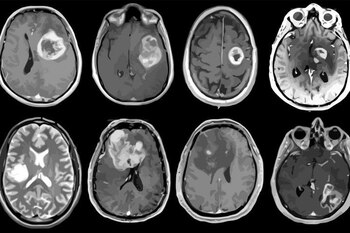

O glioblastoma é o mais comum e letal dos tumores cerebrais malignos. O tratamento padrão inclui os três eixos terapêuticos atuais: ressecção cirúrgica, radioterapia e quimioterapia com temozolomida.